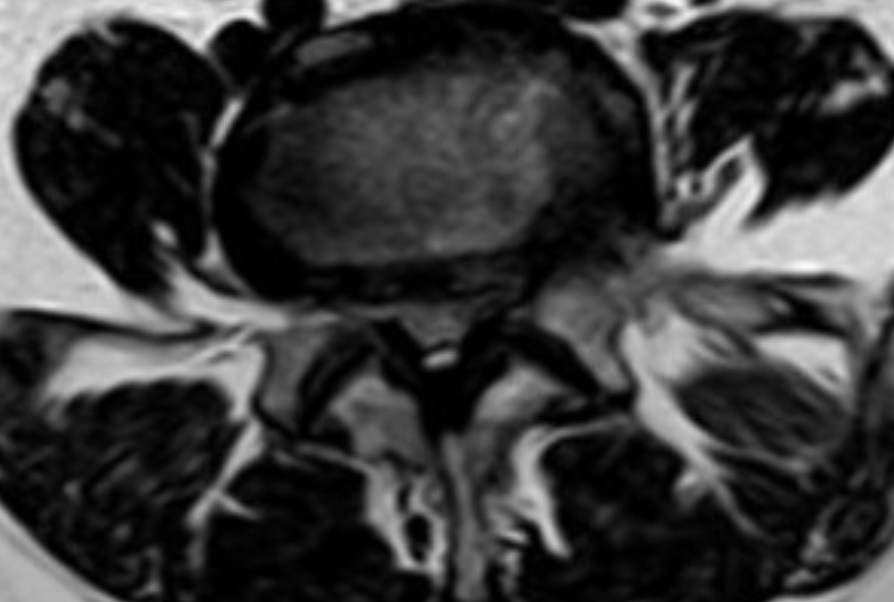

Estenosis lumbar o cervical, claudicación neurógena y planificación de descompresión dirigida.

Correlación clínico-radiológica y decisión de descompresión según síntomas y hallazgos.